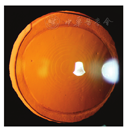

术后1 d,左眼远视力为1.0,+0.12 DS/+0.25 DC×71°,近视力为J4,眼压为17 mmHg,角膜切口对合良好,主切口轻度水肿,瓣缘处未见异常,前房中深,前房闪辉(+),瞳孔圆,对光反射灵敏,IOL居中透明。术后1周,左眼远视力为1.0,+0.25 DS,近视力为J2,眼压为16 mmHg,眼前节正常。术后1个月,左眼远视力为1.0,-0.50 DC×125°,近视力为J3,眼压为16 mmHg,眼前节正常(图2);角膜内皮细胞计数2 355个/mm2,变异系数为28,角膜曲率K1=42.375@50°,K2=42.35@140°,前节OCT可见角膜切口对合好,无水肿。